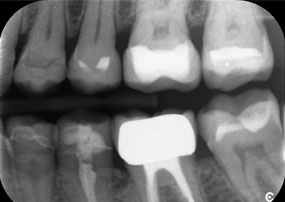

Un deuxième cas illustrant les capacités cliniques du Power Edition concernait le remplacement d'une couronne en zircone endommagée chez une patiente de 63 ans. La patiente présentait une facette ébréchée sur sa couronne en zircone vieille de 20 ans sur la dent 6. Malgré l'emplacement postérieur, la patiente trouvait le défaut gênant et demandait une nouvelle restauration.

Le Power Edition a permis un sectionnement précis, grâce à un couple accru et un refroidissement amélioré qui ont contribué à l'ablation contrôlée de la couronne sans perte importante de matière. Le système de serrage et le couple amélioré se sont avérés essentiels dans ce processus.